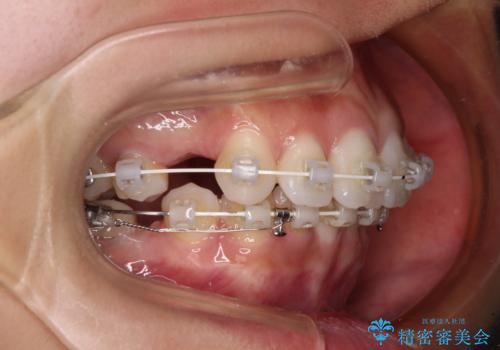

- 矯正装置

- 審美装置

補助装置を用いて上顎歯列全体を後方に移動させ、下顎は左右で抜歯する小臼歯を変えることで、左右の咬み合わせをより理想的な位置となるように計画しました。

埋伏している右下第二大臼歯は、牽引して咬合に参加させることで計画しましたが、癒着などにより移動困難な場合には、抜歯の上インプラント補綴治療を行うこととしました。